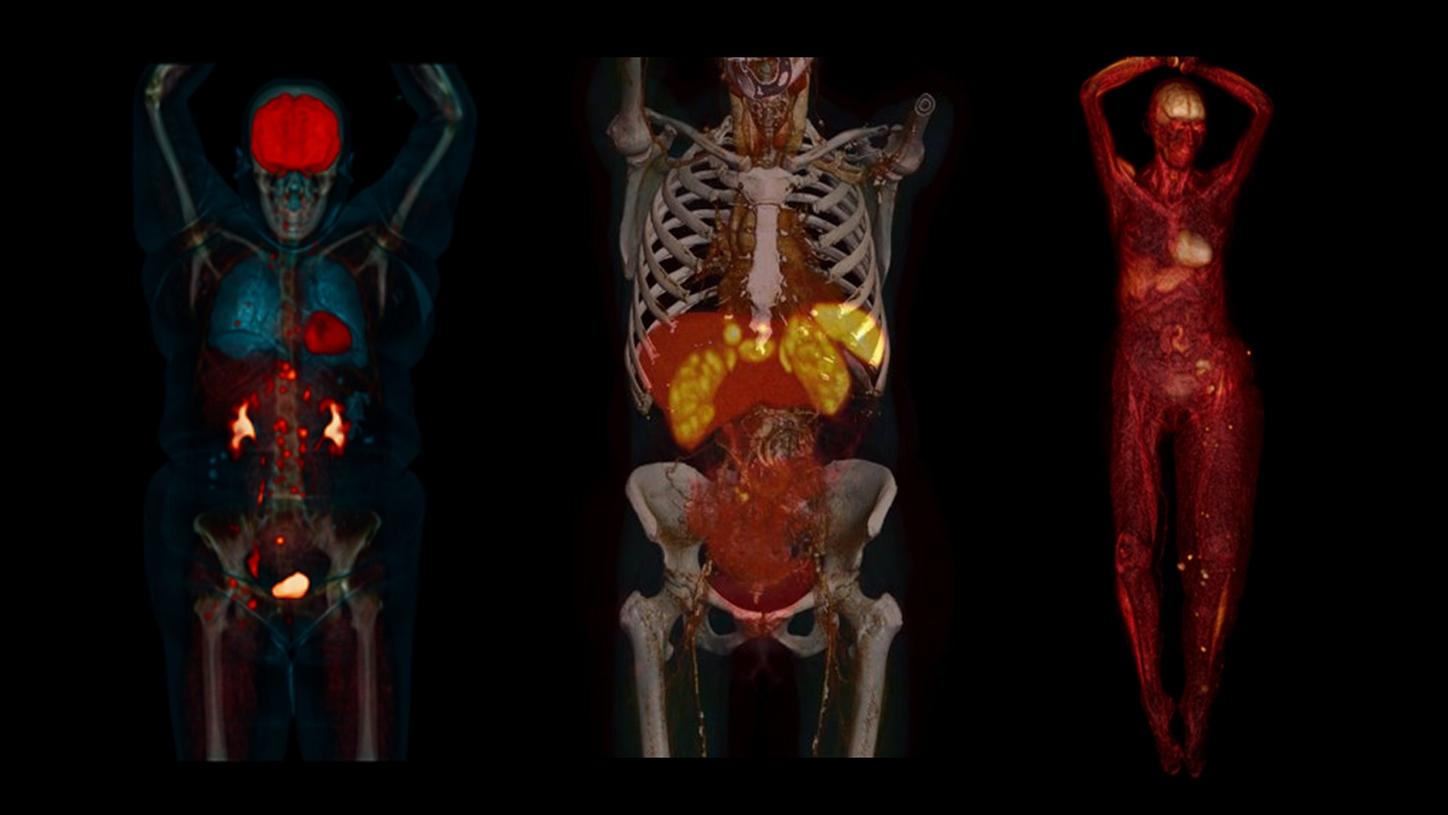

Answering to clinical needs in oncology, neurology, cardiology, and radiology, Siemens Healthineers Molecular Imaging systems provide PET/CT, SPECT, and hybrid SPECT scanner (SPECT/CT) solutions to help clinicians diagnose, treat, and monitor diseases more confidently.